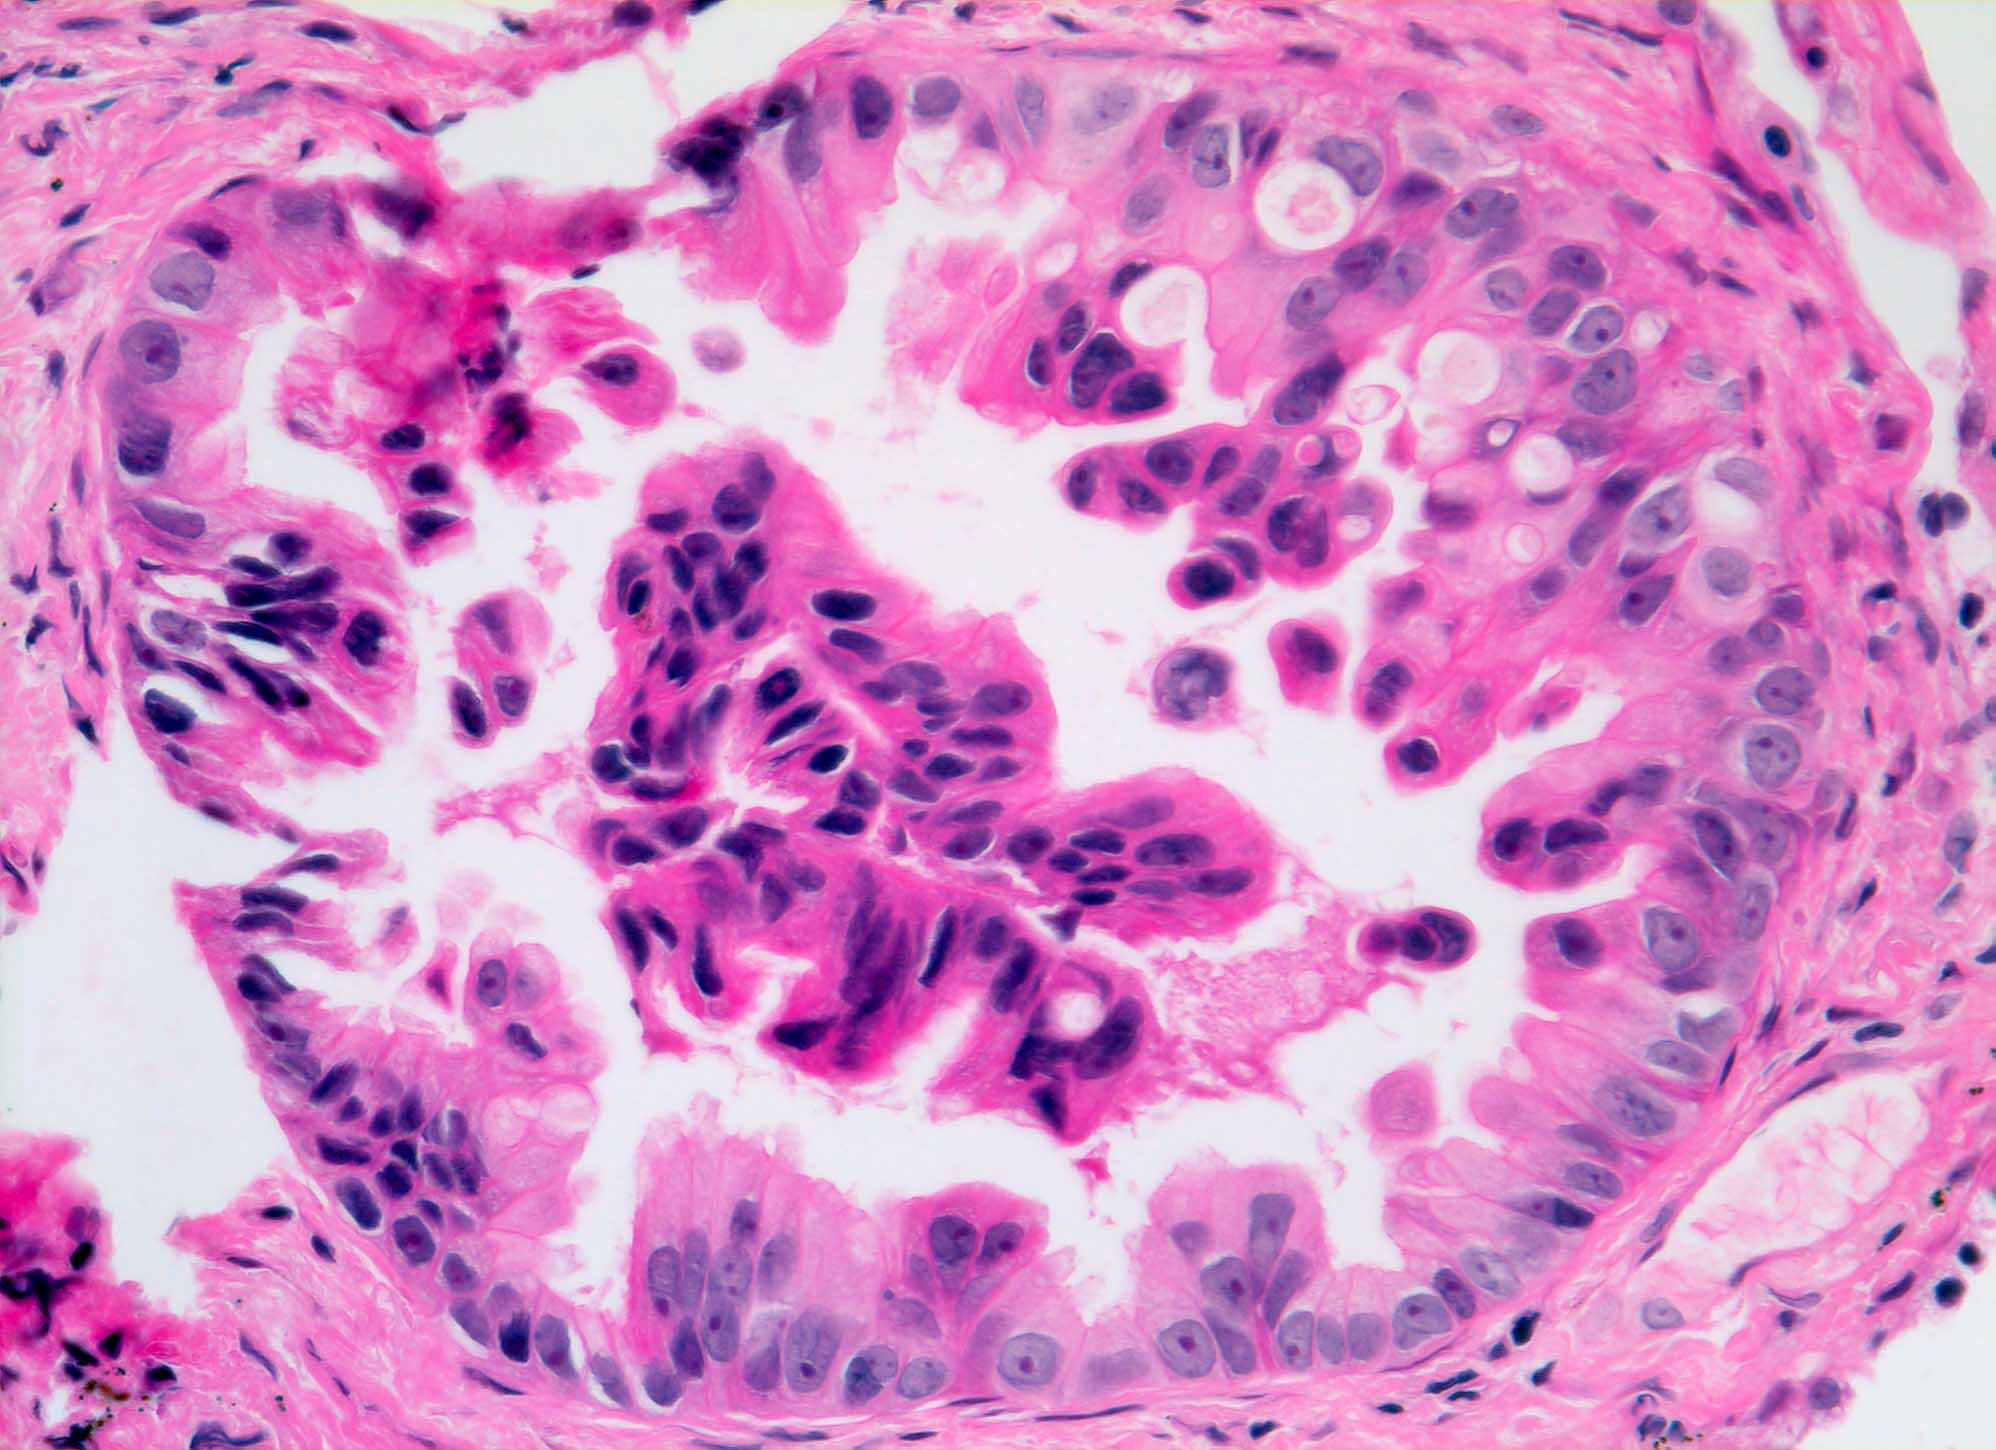

PathoPic – image database / PathoPic ID 5796 - Adenokarzinom

Adenokarzinom

maligner Tumor

Bronchus

Lunge, Mediastinum mit Thymus

Drüse ausgekleidet von atypischem Epithel mit vergrösserten basalständigen Kernen.

Autoptischer Nachweis eines primären Bronchuskarzinoms.

Multiple Lungenrundherde.

Histologie

320